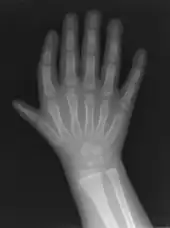

Triphalangeal thumb

Finger-like appearance

Triphalangeal thumb (TPT) is a congenital malformation where the thumb has three phalanges instead of two. The extra phalangeal bone can vary in size from that of a small pebble to a size comparable to the phalanges in non-thumb digits. The true incidence of the condition is unknown, but is estimated at 1:25,000 live births.[1] In about two-thirds of the patients with triphalangeal thumbs, there is a hereditary component.[2] Besides the three phalanges, there can also be other malformations. It was first described by Columbi in 1559.[3]

The triphalangeal thumb has a different appearance than normal thumbs. The appearance can differ widely; the thumb can be a longer thumb, it can be deviated in the radio-ulnar plane (clinodactyly), or thumb strength can be diminished. In the case of a five-fingered hand it has a finger-like appearance, with the position in the plane of the four fingers, thenar muscle deficiency, and additional length. There is often a combination with radial polydactyly.